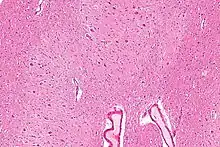

The dentate nucleus is highly convoluted, with gyri (ridges on the cerebral cortex) and sulci (furrows or grooves on the cerebral cortex). Its formation is coincident with a critical period of extensive growth in the fetal dentate. The dentate nucleus becomes visible in the cerebellar white matter as early as 11–12 weeks of gestation, containing only smooth lateral (towards the side(s) or away from the midline) and medial (towards the midline) surfaces. During this time, the neurons of the dentate nucleus are similar in shape and form, being mainly bipolar cells.[2]

During 22–28 weeks of gestation, which is the critical period in fetal development of the dentate nucleus, gyral formation occurs extensively over the entire surface.[3] Here, neurons mature into various forms of multipolar cells,[3] and the most frequent neuronal types are medium sized to large neurons.[2]

Morphology

The dentate nucleus is highly convoluted[3] and can be divided into dorsal (motor) and ventral (nonmotor) domains. The ventral half is much more developed in humans than in great apes, and it appears to play an important role in fiber connection. Further, the ventral domain mediates higher cerebellar functions, such as language and cognition, as well as versatile and coordinated finger movement.[8] While it is generally accepted that the ventral region is more recent on an evolutionary timescale, current 3-Dimensional imaging raises questions regarding this assumption, as a third axis, the rostrocaudal axis, can now be analyzed.[3] In addition, current images show that the ventral region is not physically larger than the dorsal region in humans, as would be predicted if size increases with cognitive function.[1]